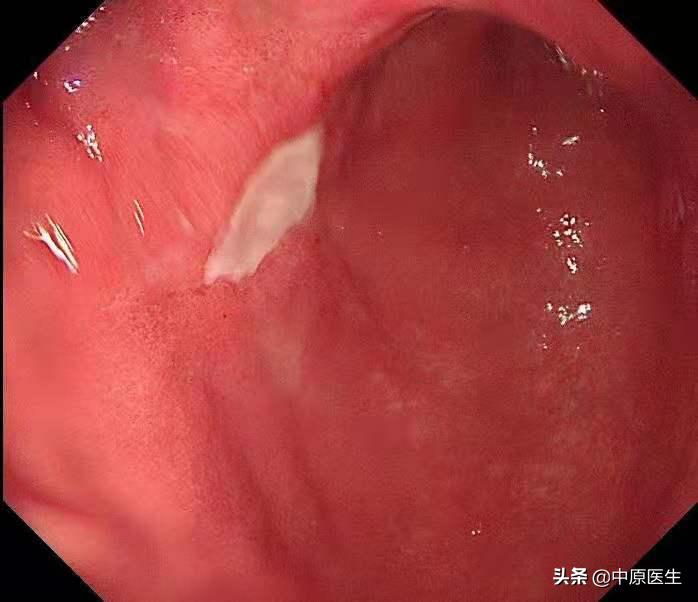

我接着按照程序仔细检查每一个角落,结果在胃角的前壁、胃窦后壁又分别发现了一个溃疡,

我心中暗暗松了一口气,因为根据既往的经验,多发溃疡,良性可能性大,或许是地方医院的病理结果不准确。